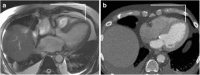

Transcatheter Aortic Valve Implantation (TAVI) is increasingly being used in patients with severe aortic stenosis who are not candidates for surgery. ECG-gated CT angiography (CTA) plays an important role in the preoperative planning for these devices. As the number of patients undergoing these procedures increases, a subset of patients is being recognized who have contraindications to iodinated contrast medium, either due to a prior severe allergic type reaction or poor renal function. Another subgroup of patients with low flow and low gradient aortic stenosis is being recognized that are usually assessed for severity of aortic stenosis by stress echocardiography. There are contraindications to stress echocardiography and some of these patients may not be able to undergo this test. Non-contrast MRI can be a useful emerging modality for evaluating these patients. In this article, we discuss the emerging indications of non-contrast MRI in preoperative assessment for TAVI and describe the commonly used MRI sequences. A comparison of the most important measurements obtained for TAVI assessment on CTA and MRI from same subjects is included. Teaching Points • MRI can be used for preoperative assessment of aortic annulus. • MRI is an alternate to CTA when iodinated contrast is contraindicated. • Measurements obtained by non-contrast MRI are similar to contrast enhanced CTA. • MRI can be used to assess severity of aortic stenosis.